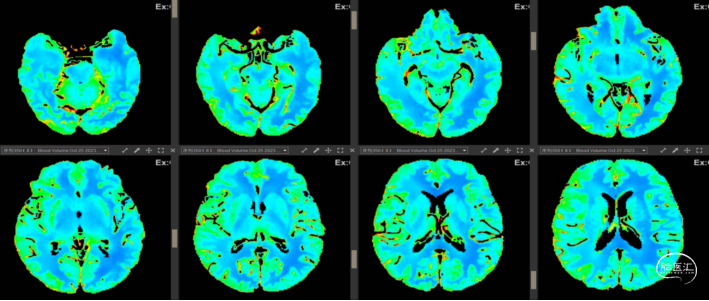

2023-10-25 术前CBF示右侧大脑中动脉供血区血流量减少。

2023-10-30 术后CBF示右侧大脑中动脉供血区血流量恢复正常。

2015年多项试验(MR CLEAN、ESCAPE、SWIFT PRIME、REVASCAT和 EXTEND IA)证实了血管内机械取栓术在治疗前循环大血管闭塞卒中方面优于药物治疗,2017年,DAWN和DEFUSE-3试验成功地将患者的时间窗延长至24小时[1]。患者为发病15小时入院,已超溶栓时间窗,通过CTP可见右侧大脑半球CBF、MTT、TMax延长,CTA未见明显狭窄,故考虑行脑动脉造影术明确责任血管,脑动脉造影术中发现右侧大脑中动脉M1末段以远动脉早期、中期、晚期血流速减慢,与家属沟通后,尝试SWIM技术抽拉一次,可见微量血栓,后造影提示右侧大脑中动脉及以远动脉早期、中期、晚期血流速明显恢复正常;3D造影未见明显狭窄,考虑为血栓事件。